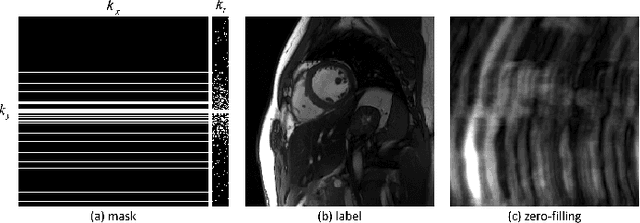

Abstract:Deep learning has achieved good success in cardiac magnetic resonance imaging (MRI) reconstruction, in which convolutional neural networks (CNNs) learn the mapping from undersampled k-space to fully sampled images. Although these deep learning methods can improve reconstruction quality without complex parameter selection or a lengthy reconstruction time compared with iterative methods, the following issues still need to be addressed: 1) all of these methods are based on big data and require a large amount of fully sampled MRI data, which is always difficult for cardiac MRI; 2) All of these methods are only applicable for single-channel images without exploring coil correlation. In this paper, we propose an unsupervised deep learning method for parallel cardiac MRI via a time-interleaved sampling strategy. Specifically, a time-interleaved acquisition scheme is developed to build a set of fully encoded reference data by directly merging the k-space data of adjacent time frames. Then these fully encoded data can be used to train a parallel network for reconstructing images of each coil separately. Finally, the images from each coil are combined together via a CNN to implicitly explore the correlations between coils. The comparisons with classic k-t FOCUSS, k-t SLR and L+S methods on in vivo datasets show that our method can achieve improved reconstruction results in an extremely short amount of time.